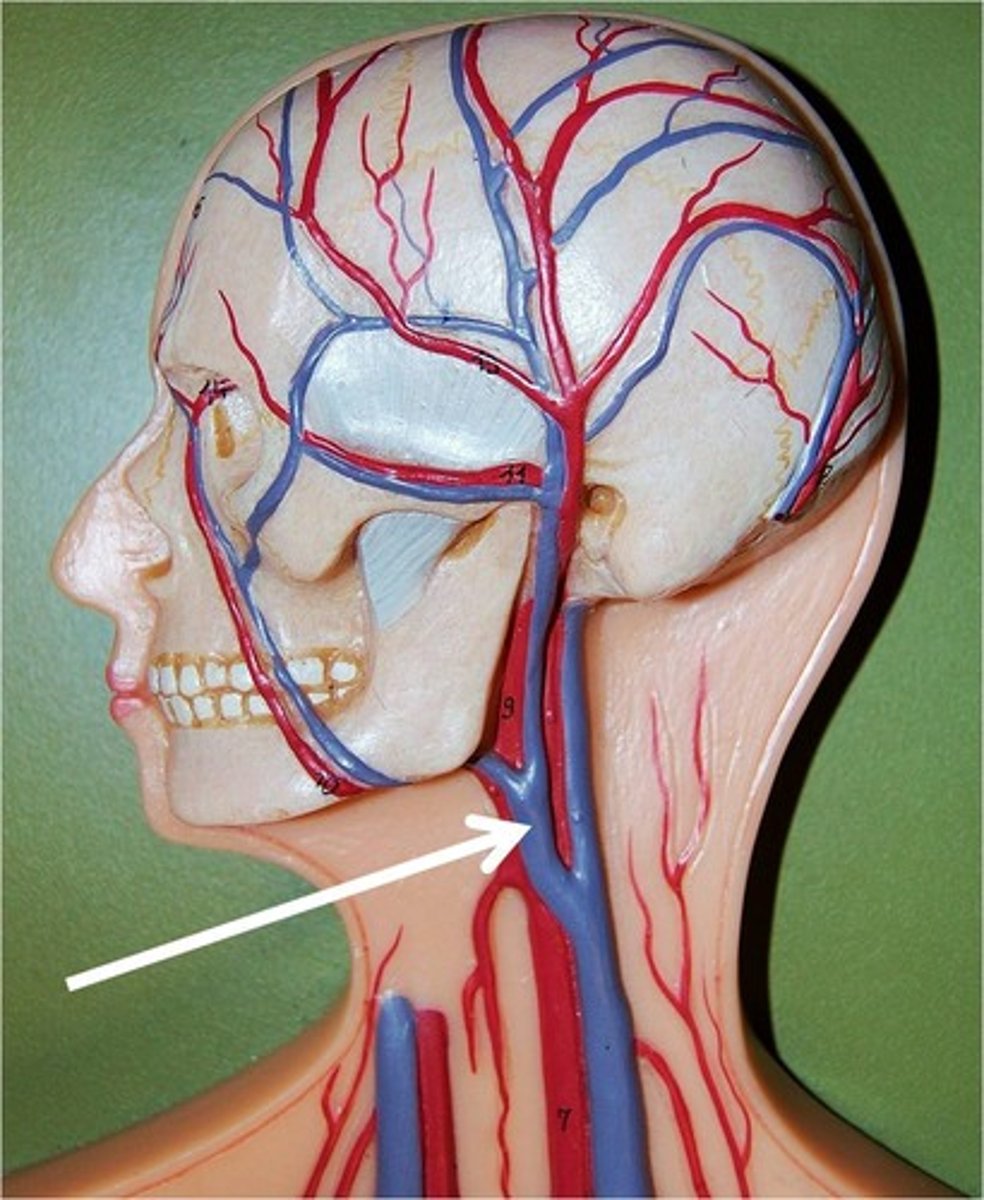

Common carotid artery